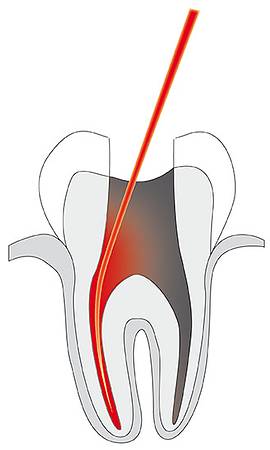

- Endodontie

- Endodontie

© Cumdente